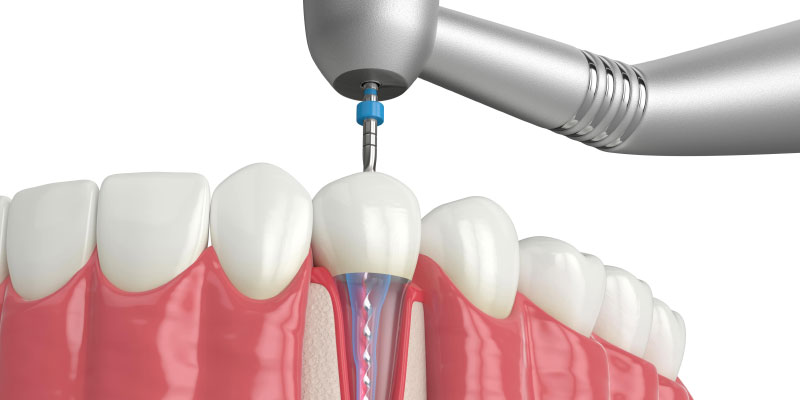

Cleaning &

Shaping

Infected pulp is removed, and root canals are cleaned and shaped.